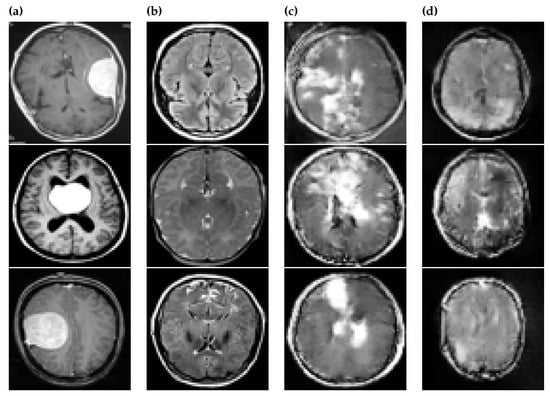

Our results are summarized in Table 2 and Table 3, and Figure 3 also shows examples from training data and GAN-generated images. Table 2 contains the mean values of the 20 accuracy values computed from original and GAN-generated images when either no GAN-generated images or up to 1000 GAN-generated images. The results show a maximum mean accuracy of 88% with a 3% standard deviation when 1000 original images and 500 GAN-generated images were tested.

Figure 3.

Examples of the following are given: (a) Positive images in the original dataset; (b) Negative images in the original dataset; (c) Positive images created by GAN; (d) Negative images created by GAN.

Table 3 tells us about the significant difference between original and GAN-generated images using the Mann–Whitney U-test. According to Table 3, there are statistically significant differences between the datasets when 250, 500, and 750 GAN-generated images are added with training data of 50, 500, and 1000 original images. Comparing this to Table 2, we see that the highest values of accuracy are obtained with 250, 500, and 750 GAN-generated images with 1000 original images, so the use of GAN augmentation also significantly increased the accuracy in these cases. However, adding more GAN data was not always helpful, and, in particular, adding 10 GAN-generated images to 500 original images significantly decreased the accuracy.